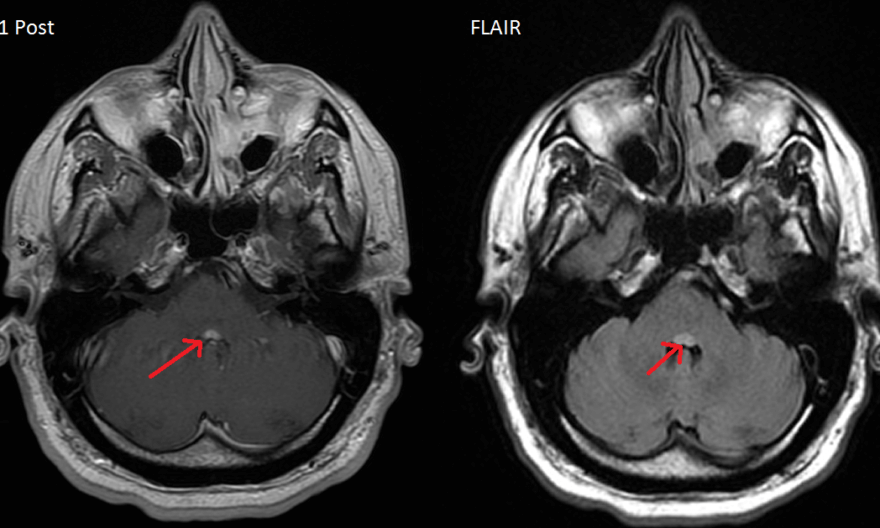

The facial colliculi sit on the dorsal aspect of the pons, forming part of the floor of the fourth ventricle. Both facial colliculi are highlighted in the image below.

Lesions that affect bilateral facial colliculi are rare, but in the case shown here both are affected by what is likely multiple sclerosis or other demyelinating disease (positive oligoclonal bands and other non-enhancing periventricular white matter lesions). The effects of a lesion are determined by the structures that constitute the facial colliculus, specifically the nucleus of the abducens nerve (CN VI), the facial nerve that wraps around the abducens nucleus, the paramedian pontine reticular formation (PPRF) that sits near the abducens nucleus, and the medial longitudinal fasciculus (MLF).